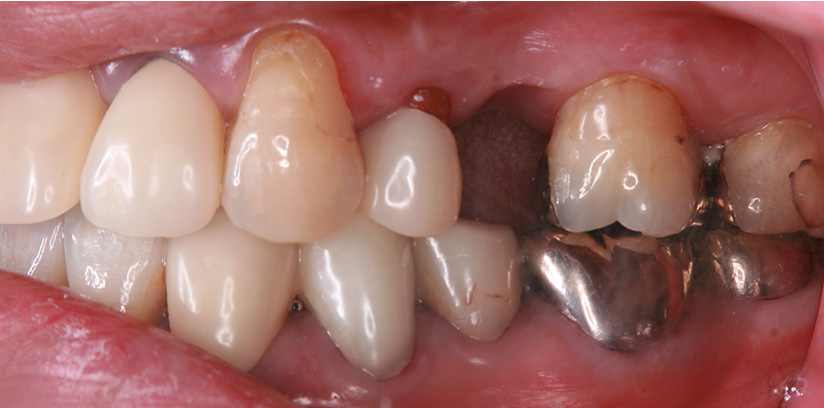

症例紹介

1歯義歯治療の例

術前・術後の比較

| 患者属性 | 50代 女性 |

|---|---|

| 主訴 | 左上の歯ぐきが痛む |

| 診断 | 左上5 歯根破折 |

| 補綴装置 | ノンクラスプデンチャー |

| 治療期間 | 約2ヵ月 |

| 通院回数 | 2回 |

| 治療費 | ノンクラスプデンチャー治療(1歯):110,000円(税込) |

| 治療内容 | 左上5の抜歯術を行い、治癒期間(約1か月)を得て、2回の義歯治療で義歯を作成しています。 |

| リスクと副作用 | 歯がないところの横の歯(隣在歯)に義歯をひっかけるため、その支えとなる歯には、ブリッジ治療と同様の影響があります。 |